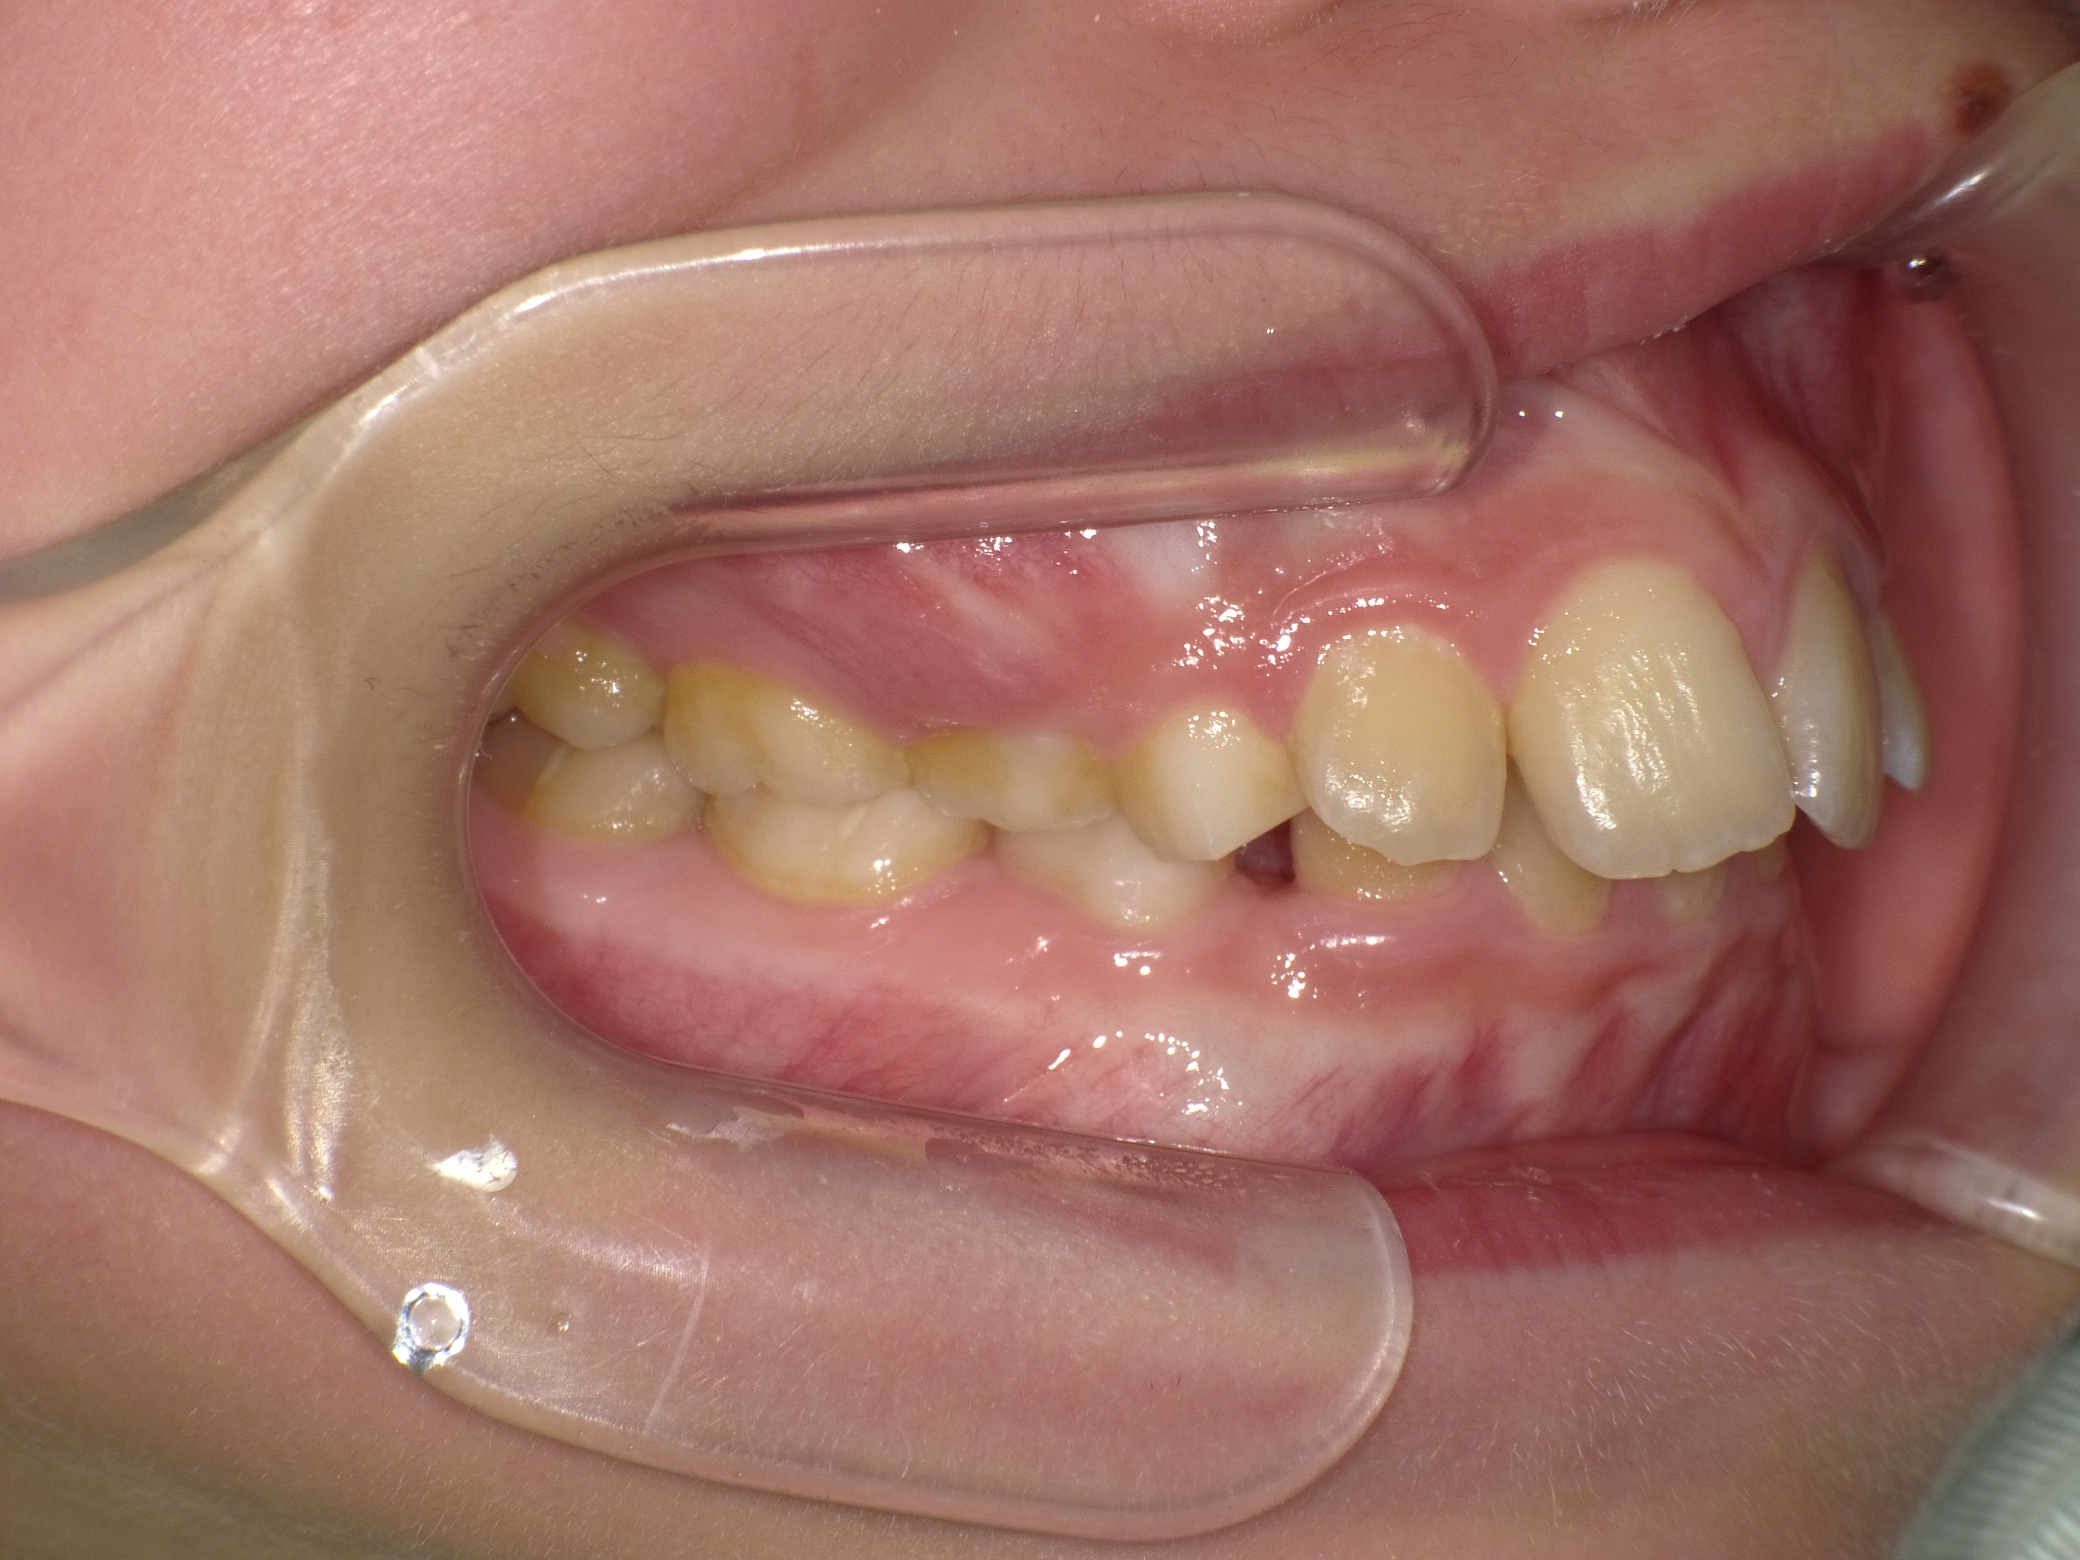

【小学生】 マイオブレース矯正 上顎前突(出っ歯)を改善

小学生で開始

マイオブレース

出っ歯

過蓋咬合

非抜歯

1期治療のみで改善

Before

After

治療期間

2年

治療開始

10歳

種類

マイオブレース矯正

使用装置

コメント

装置の装着と MFT(筋機能療法)をしっかり取り組んでくれました。

舌癖もなおり、後戻りもありません。